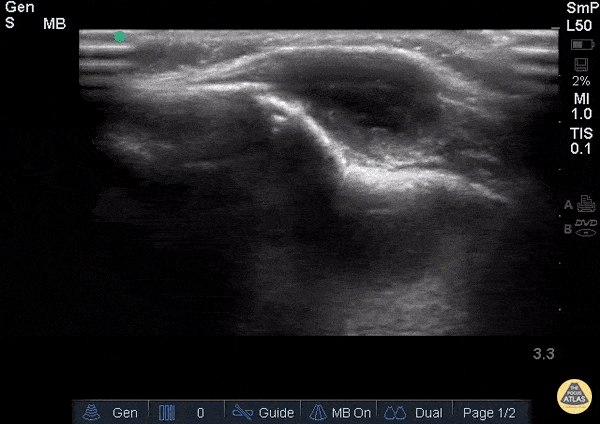

WCUME 2017 Submission for "Novel Indication" Face mass with bone erosion due to tuberculosis. Dr. Atim Uya - San Diego, California